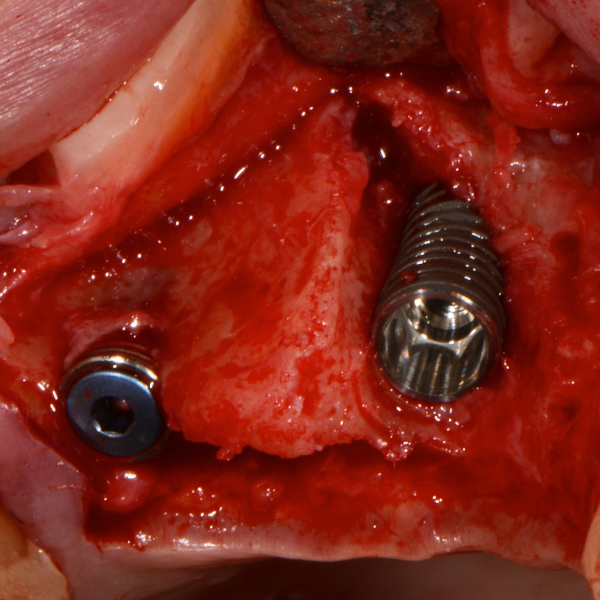

Tooth 14 slightly increased mobility, tenderness and bite pain. Suspected root fracture